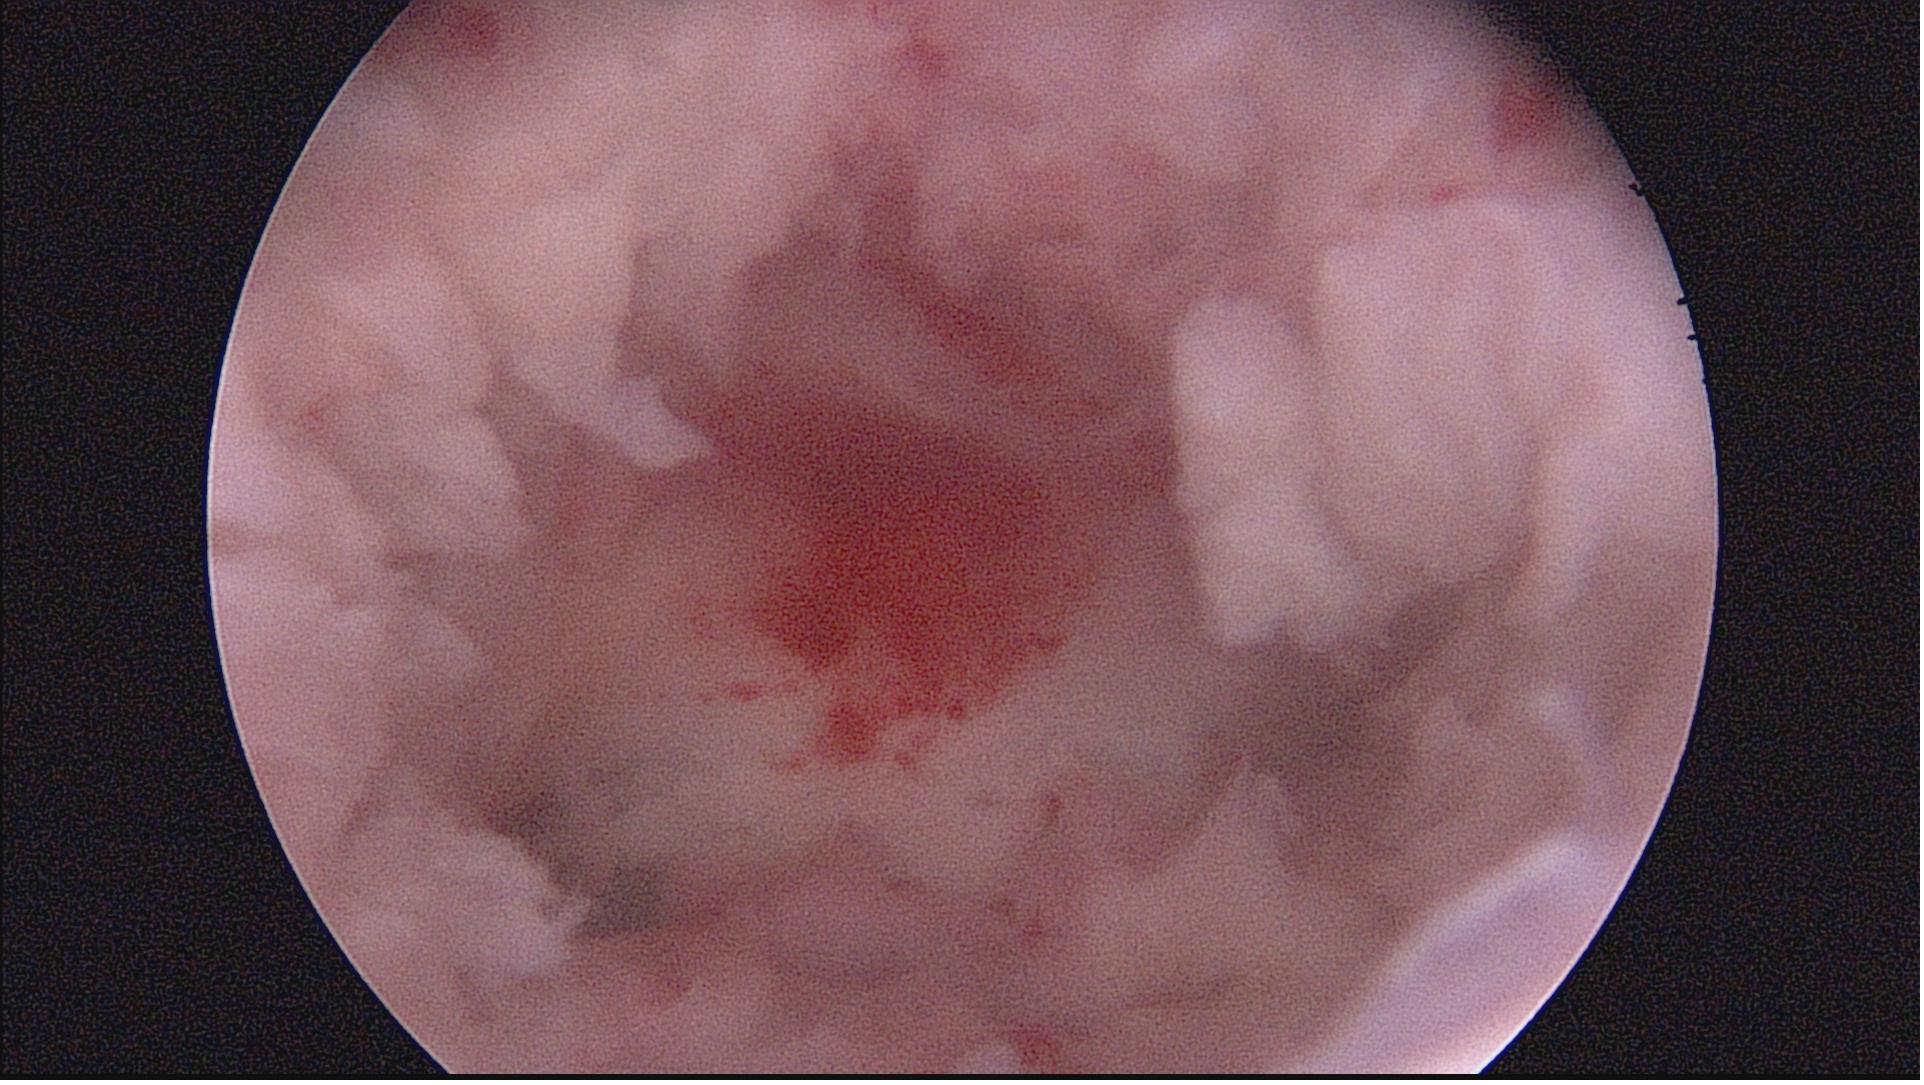

重度宫腔粘连术前图片

图一:宫腔疤痕